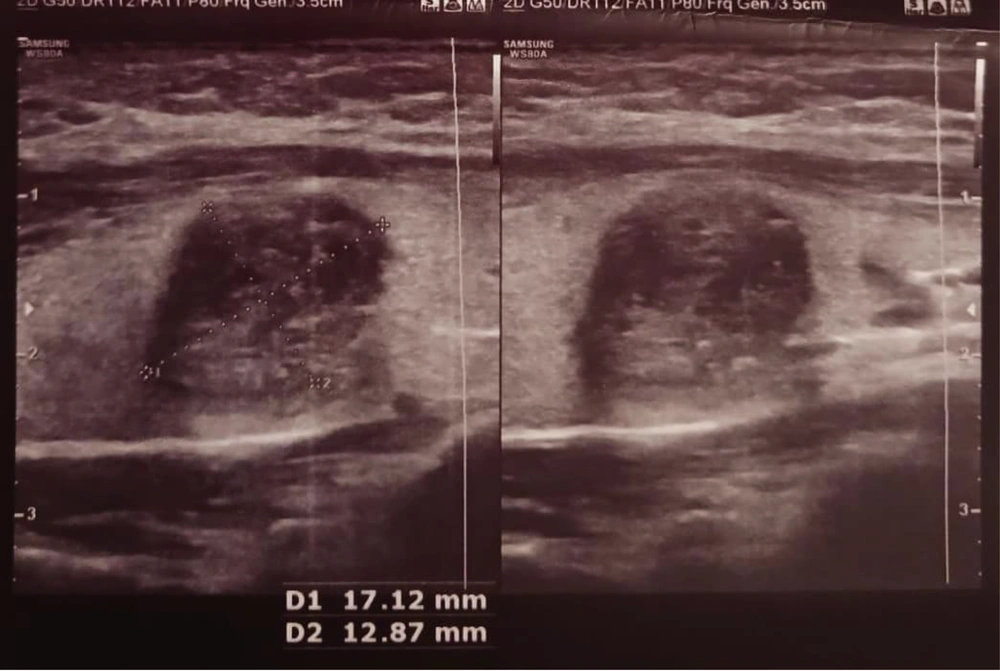

A 26-year-old female patient presented to our hospital with a 3-month history of progressive pain and swelling in the anterosuperior neck, predominantly on the right side. On the patient’s physical examination, a soft, mobile nodule approximately 3 × 2 cm in size was palpated in the right lobe of the thyroid gland. Cervical lymphadenopathy was detected, and examinations of other systems were normal. Blood tests and thyroid tests were within normal limits. The thyroid US revealed a hypoechoic, fluid-filled lesion with internal echoes and thick internal septations, measuring 41 × 36 × 28 mm and with a volume of 22 cc, suggestive of a conglomerate necrotic lymph node (Level III-IVa, Figure 1). Additionally, a hypoechoic nodule, wider than tall, with well-defined borders and peripheral and punctate calcifications measuring 17 × 13 mm was observed (TIRADS V, Figure 2). The FNA of this nodule was suspicious for PTC. Consequently, the patient underwent bilateral total thyroidectomy. No intraoperative and postoperative complications developed. After surgery, the patient was prescribed albendazole 40 mg twice a day, and her symptoms improved. The patient is being followed up without any recurrence. A CT scan of the chest, abdomen, and pelvis performed after total thyroidectomy revealed evidence of hydatid cysts in the liver and spleen but no hydatid cysts in the lungs (Figure 3A - C ).

A hypoechoic, wider-than-tall nodule with smooth borders and peripheral and punctate calcifications measuring 17 × 13 mm is seen in the right lobe of the thyroid gland (TIRADS = 5). According to the fine needle aspiration (FNA) performed on the nodule, it was reported as suspicious for papillary thyroid carcinoma (PTC).